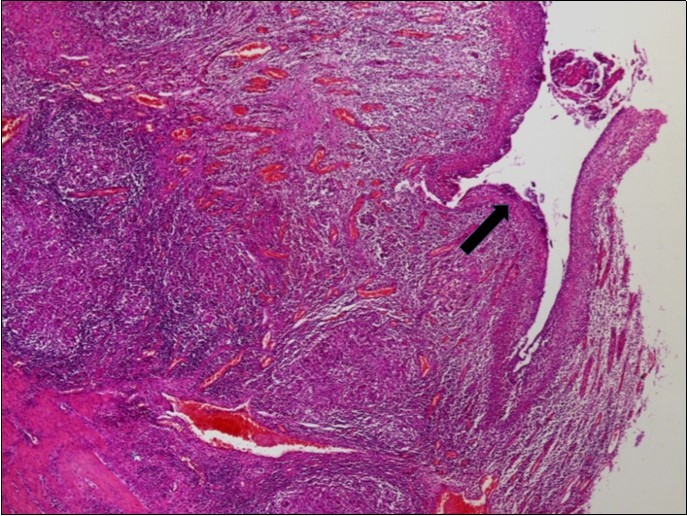

The histopathologic examination of the resected bowel specimen showedcaseating granulomatous inflammation (Figure 2), consistent with intestinal small bowel tuberculosis complicated with peritonitis and perforation (Figure 3).

Figure 3.Signs of acute peritonitis in the intestinal mucosa